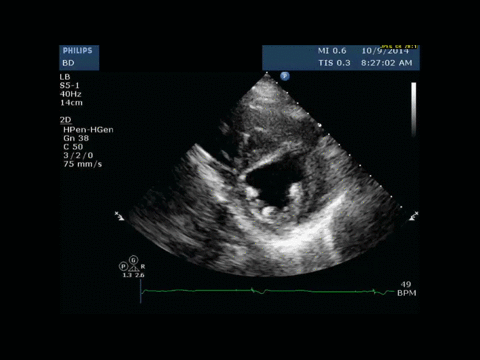

History of Present Illness: A 73-year-old female presents to the emergency room with a 3-day-history of chest pain and hallucinations. She is initially treated for urinary tract sepsis, however eight hours after presentation, she suddenly became unresponsive and hypotensive, requiring intubation and initiation of vasopressors. Initial focused-bedside ultrasound aiming to evaluate etiologies of shock reveals septal wall hypokinesia.

With worsening hypotension, serial bedside ultrasound was performed.